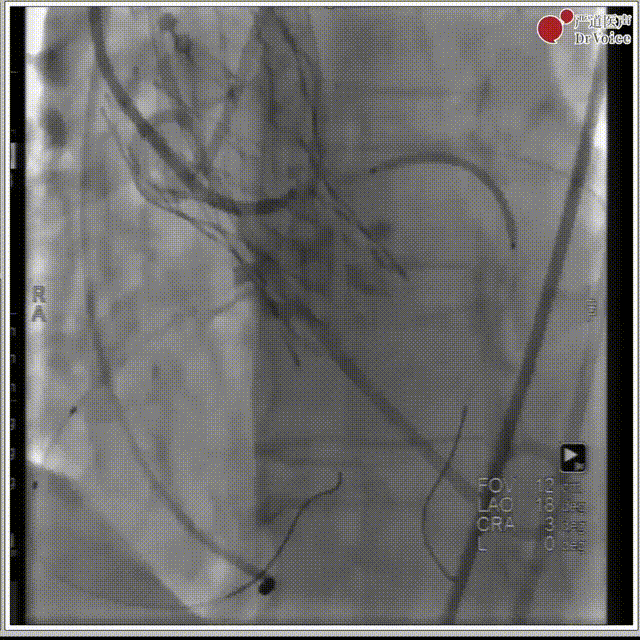

1. 冠脉造影。

冠脉造影图片1

冠脉造影图片2

2. 冠脉保护,左冠预埋支架。

冠脉保护后造影